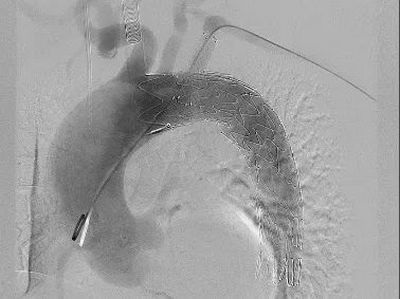

▲ 经肱动脉穿刺破膜

手术方式确定后,快速完成术前准备,在全麻下行在其胸主动脉植入覆膜支架,同时在左锁骨下动脉原位开窗,植入分支支架。体内开窗完成仅用几秒钟,整个手术过程耗时2小时,患者只是在右股部开2mm的穿刺口和左上肢3cm的切口。术后,患者意识清醒安全返回病房,2天后即可下床活动,手术取得了良好的治疗效果。